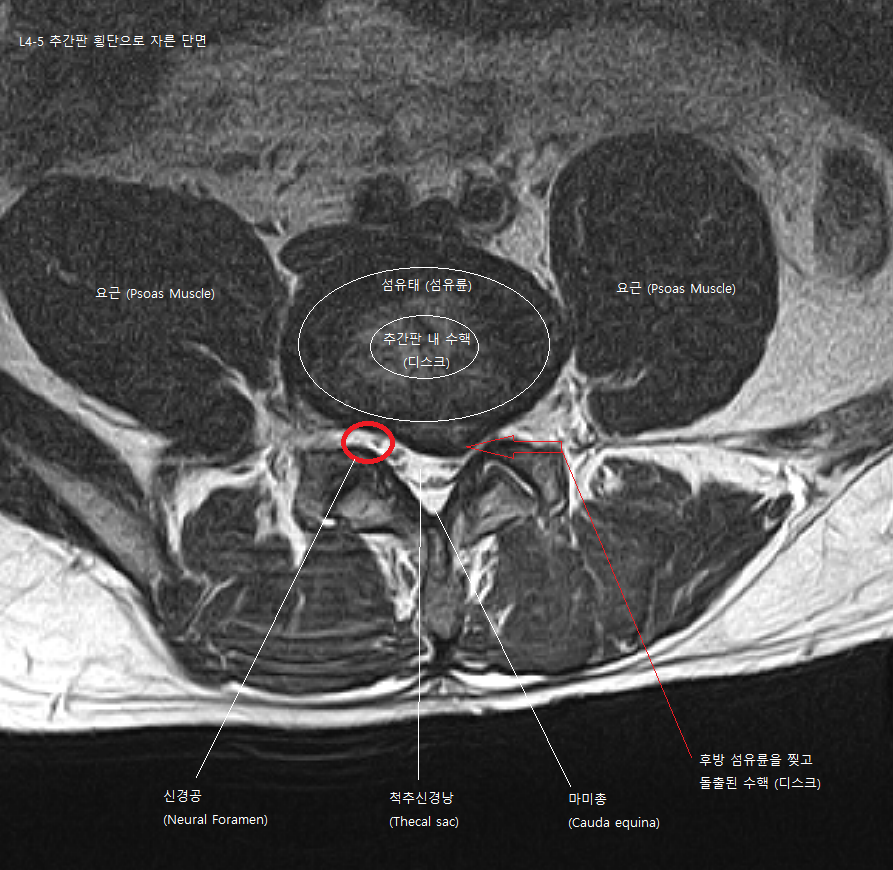

3. MRI 단면도 보는 방법

위 사진은 L4-L5 요추 MRI T2 영상 단면 이미지입니다. 말 그대로 탈출된 4 번호 5번 사이의 디스크를 단면으로 자른 영상을 보여주는 것입니다. 디스크 수핵과 섬유륜 조직을 확인할 수 있고, 돌출이나 탈출된 디스크로 인해 척 수낭을 기계적으로 압박하는지 또한 다리 쪽으로 내려가는 신경공을 좁게 많드는지 등을 확인할 수 있습니다. 정상적인 디스크 단면이라면 척추 신경낭 부분이 하얀 역삼각형 모양인데 디스크 탈출로 인해 한쪽면이 압박받고 있는 것을 확인할 수 있습니다.